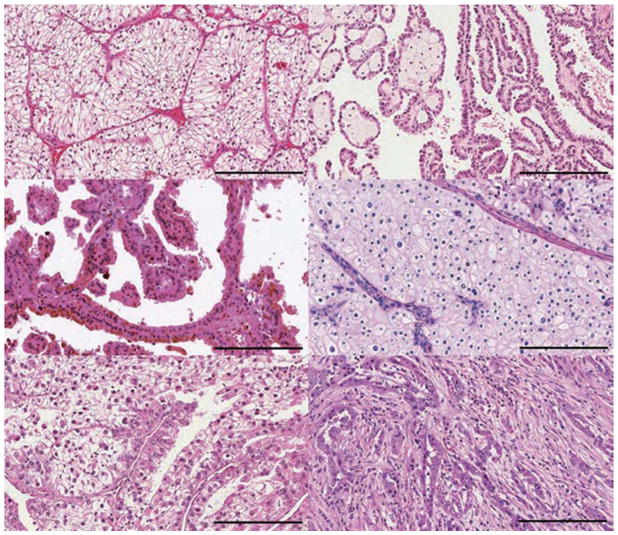

约75%的肾细胞癌(RCC)是透明细胞RCC(ccRCC)。乳头状RCC约占所有肾癌的15%,根据染色特征分为两种类型:I型(嗜碱性)和II型(嗜酸性)。嫌色性肾细胞癌约占肾肿瘤的5%。其他次要亚型包括MiT家族易位RCC和集合管RCC。其他次要亚型包括髓质RCC、透明细胞乳头状RCC、获得性囊性疾病相关RCC、肾小管细胞RCC、黏液性肾小管和梭形RCC、琥珀酸脱氢酶缺陷RCC、遗传性平滑肌瘤病、肾细胞癌相关RCC和嗜酸细胞瘤。不属于这些类别的肿瘤被指定为非分类肾细胞癌。

肾细胞癌 (RCC) 包括一组源自肾小管上皮细胞的异质性癌症,是全球 10 种最常见的癌症之一。 在过去二十年中,肾细胞癌 (RCC)的组织病理学和分子表征方面的重要进展导致对其分类进行了重大修订。 发病率≥5% 的主要亚型是透明细胞肾细胞癌 RCC (ccRCC)、乳头状肾细胞癌 RCC (pRCC)和嫌色细胞肾细胞癌 RCC (chRCC)(图 1)。 其余亚型非常罕见(每种亚型的总发病率≤1%),如果肿瘤不符合任何亚型诊断标准,则将其归为未分类 RCC(uRCC,总发病率约为 4%)。 透明细胞肾细胞癌是最常见的亚型,占肾癌死亡的大部分,是佳学基因肾细胞癌基因检测的重点。 事实上,由于透明细胞组织学在转移性疾病中占主导地位 (83-88%),具有非透明细胞组织学的肿瘤已被归类为“nccRCC”(表 1),以便进行临床试验的可行性。 此外,最近的癌症基因组研究揭示了 ccRCC 肿瘤内和肿瘤间异质性的明显复杂性,这可能导致观察到的异质性临床结果。